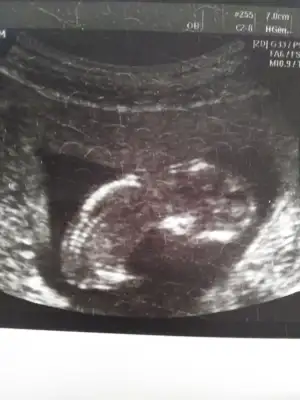

Cinsiyetimiz nedir sizce :)

Eklentiler

• Screenshot_20191030-081838_Video Player.webp

Screenshot_20191030-081838_Video Player.webp

17,3 KB · Görüntüleme: 95